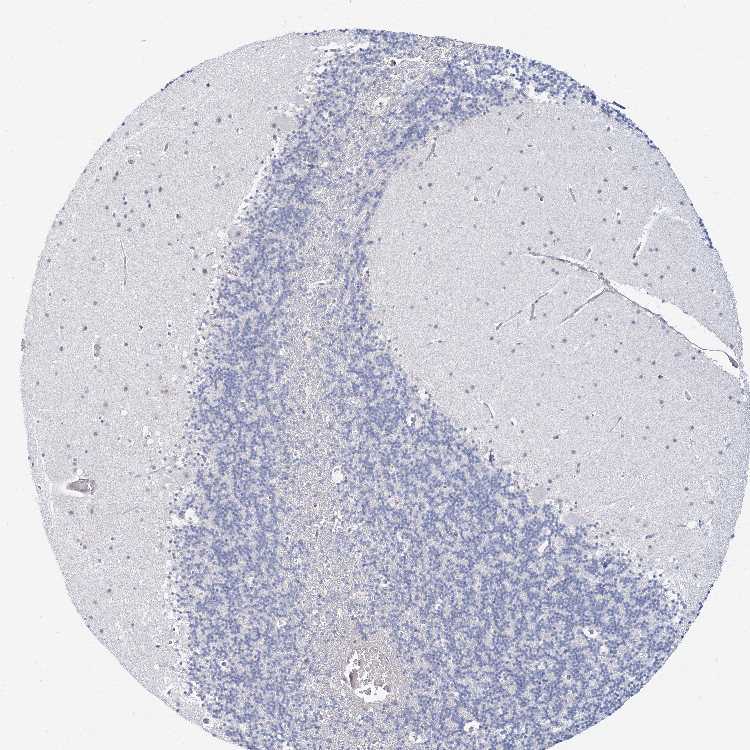

CEREBELLUM - Antibody stainingi

Antibody staining in the annotated cell types in the current human tissue is reported as not detected, low, medium, or high, based on conventional immunohistochemistry profiling in selected tissues. This score is based on the combination of the staining intensity and fraction of stained cells.

Each image is clickable and will lead to virtual microscopy that enables deeper exploration of all samples and also displays staining intensity scores, fraction scores and subcellular localization as well as patient and tissue information for each sample.

Antibody HPA035512Antibody HPA035513

Purkinje cells Not detectedNot detected

Cells in granular layer MediumNot detected

Cells in molecular layer Not detectedNot detected